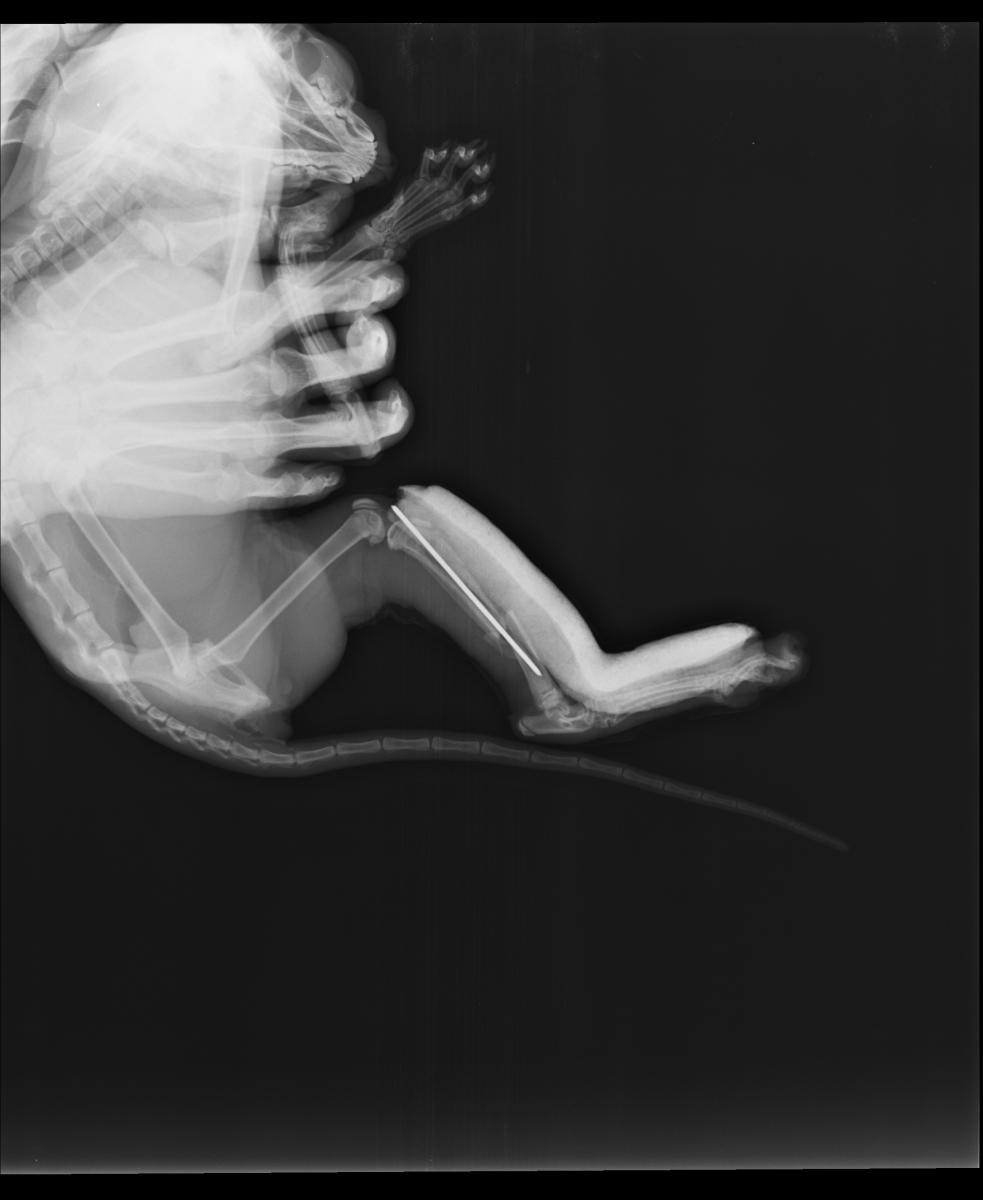

cat_X-ray_photo.jpg

Судя по снимку, кошке однозначно показана операция.

Врач сообщил, что при таком характере перелома, как на снимке выше, остеосинтез желательно проводить накостными пластинами. Он же сказал, что в Подольске с пластинами никто не работает.

Другой врач высказал сомнение в возможности использования пластин из-за миниатюрных размеров кости.

История закончилась хорошо. Кость срослась, спица в ней никак не мешает движению и не дала осложнений.

На снимке - состояние через 80 дней после операции.

Хочу отметить, что в Подольске все клиники используют только метод остеосинтеза спицами. Если перелом со множеством осколков, то фиксировать их лучше другими методами, то есть придётся везти животное в клинику в другой город.